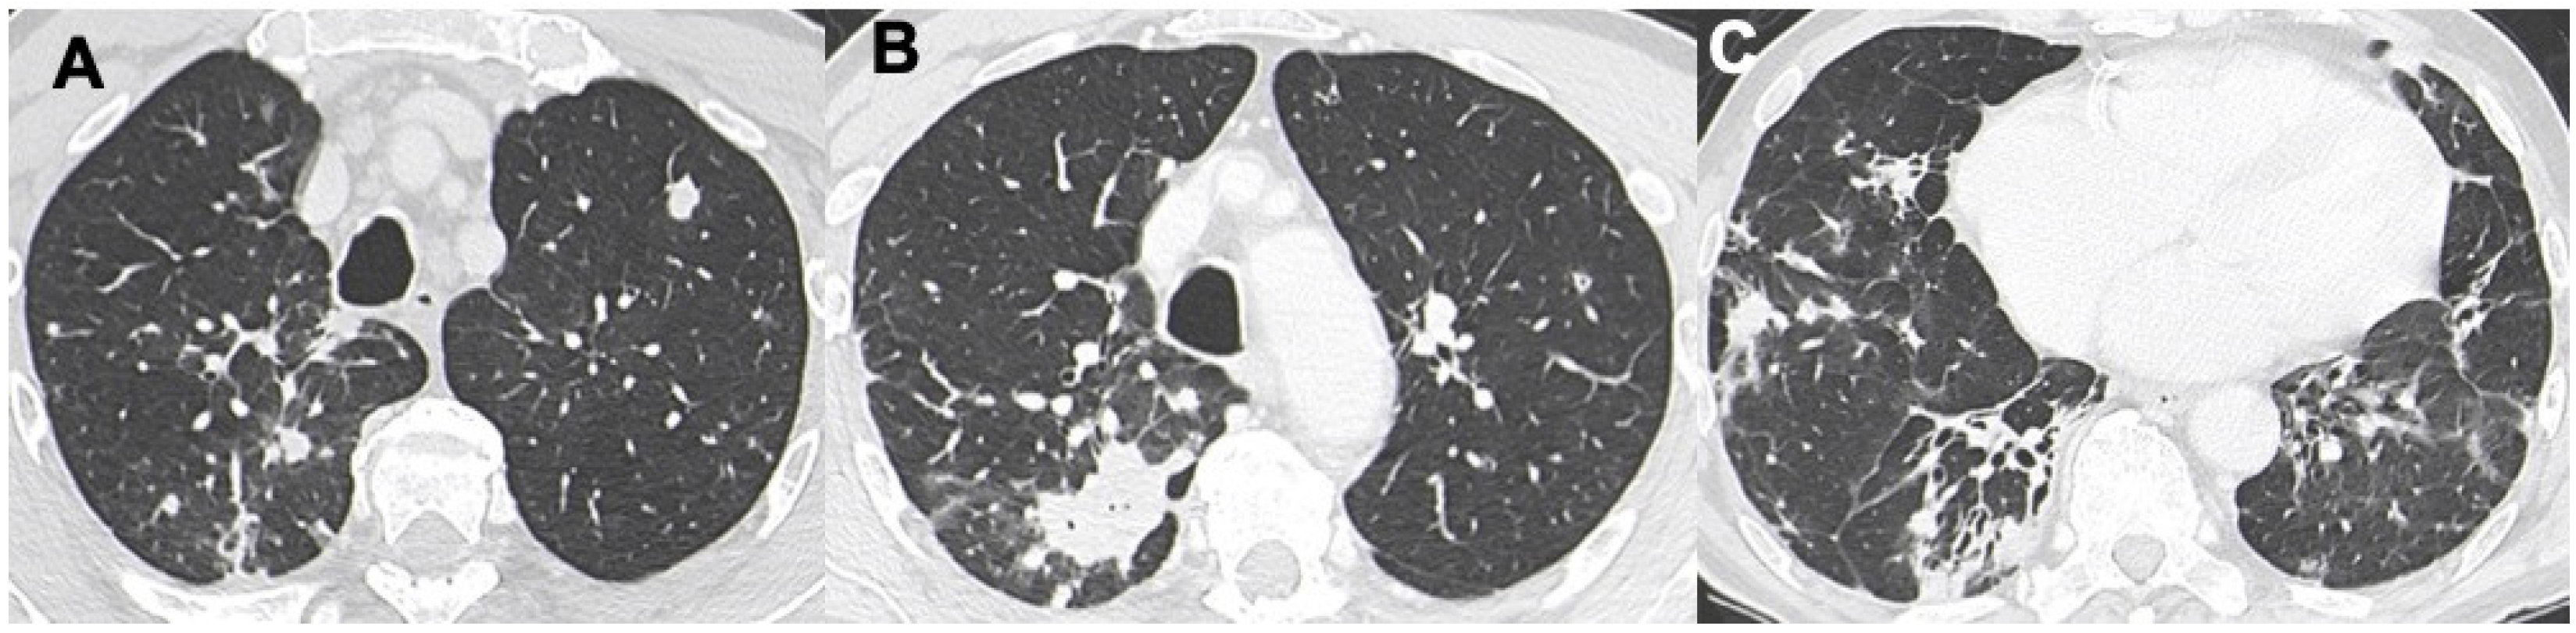

3.1. Consolidations

- Albano, D.; Borghesi, A.; Bosio, G.; Bertoli, M.; Maroldi, R.; Giubbini, R.; Bertagna, F. Pulmonary mucosa-associated lymphoid tissue lymphoma: F-FDG PET/CT and CT findings in 28 patients. Br. J. Radiol. 2017, 90, 20170311. [Google Scholar] [CrossRef]

- Deng, W.; Wan, Y.; Yu, J.Q. Pulmonary MALT Lymphoma has variable features on CT. Sci. Rep. 2019, 9, 8657. [Google Scholar] [CrossRef]

- King, L.J.; Padley, S.P.; Wotherspoon, A.C.; Nicholson, A.G. Pulmonary MALT lymphoma: Imaging findings in 24 cases. Eur. Radiol. 2000, 10, 1932–1938. [Google Scholar] [CrossRef]

- Borie, R.; Wislez, M.; Antoine, M.; Copie-Bergman, C.; Thieblemont, C.; Cadranel, J. Pulmonary mucosa-associated lymphoid tissue lymphoma revisited. Eur. Respir. J 2016, 47, 1244–1260. [Google Scholar] [CrossRef] [PubMed]

- Wislez, M.; Cadranel, J.; Antoine, M.; Milleron, B.; Bazot, M.; Mayaud, C.; Carette, M.F. Lymphoma of pulmonary mucosa- associated lymphoid tissue: CT scan findings and patholo- gical correlations. Eur. Respir. J. 1999, 14, 423–429. [Google Scholar] [CrossRef] [PubMed]

- Chen, Y.; Chen, A.; Jiang, H.; Zhang, Y.; Zhu, L.; Xia, C.; Yu, H. HRCT in primary pulmonary lymphoma: Can CT imaging phenotypes differentiate histological subtypes between mucosa-associated lymphoid tissue (MALT) lymphoma and non-MALT lymphoma? J. Thorac. Dis. 2018, 10, 6040–6049. [Google Scholar] [CrossRef]

- McCulloch, G.L.; Sinnatamby, R.; Stewart, S.; Goddard, M.; Flower, C.D. High-resolution computed tomographic appearance of MALToma of the lung. Eur. Radiol. 1998, 8, 1669–1673. [Google Scholar] [CrossRef] [PubMed]

- Cozzi, D.; Dini, C.; Mungai, F.; Puccini, B.; Rigacci, L.; Miele, V. Primary pulmonary lymphoma: Imaging findings in 30 cases. Radiol. Med. 2019, 124, 1262–1269. [Google Scholar] [CrossRef]

- Bligh, M.P.; Borgaonkar, J.N.; Burrell, S.C.; MacDonald, D.A.; Manos, D. Spectrum of CT findings in thoracic extranodal non-Hodgkin lymphoma. Radiographics 2017, 37, 439–461. [Google Scholar] [CrossRef]

- Vincent, J.M.; Ng, Y.Y.; Norton, A.J.; Armstrong, P. CT “angiogram sign” in primary pulmonary lymphoma. J. Comput. Assist. Tomogr. 1992, 16, 829–831. [Google Scholar] [CrossRef] [PubMed]